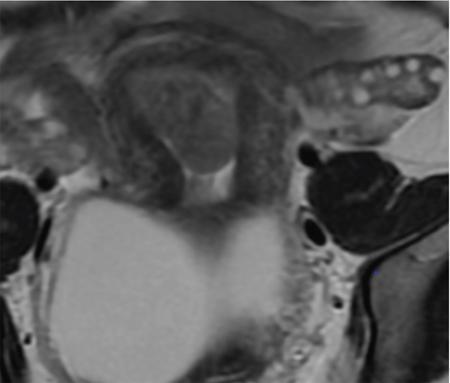

John De Lindsay, Usha Nandini Ganeshan, Vidya CERVICITIS Acute or chronic inflammation of cervix is termed as cervicitis. Noninfectious causes of cervicitis include trauma, pelvic radiation and chemical irritation. Most acute cervicitis is secondary to an infectious agent, commonly Trichomonas vaginalis, Candida albicans, herpes simplex virus, Neisseria gonorrhoeae and Chlamydia trachomatis. Patients usually present with purulent or mucopurulent cervical and vaginal discharge and may complain of pelvic pressure or discomfort. The cervix in patients with acute cervicitis shows a diffusely heterogeneous echotexture of the cervical mucosa and stroma, but the key finding is markedly increased vascularity on colour Doppler. Absence of mass is the differentiating feature between inflammation and malignancy. Free fluid can also be seen in the pouch of Douglas. CT may demonstrate an enlarged uterine cervix, an abnormally enhancing endocervical canal, and parametrial fat stranding. Retention cysts of the uterine cervix are termed as nabothian cysts. They are formed as a result of the healing process of chronic cervicitis. They are usually less than 1 cm, incidentally detected at imaging and are considered a normal finding in multiparous women. They may enlarge and become symptomatic because of mass effect, but this happens infrequently Majority of nabothian cysts, appear as small, simple anechoic cysts in the cervix, with no internal vascularity (Fig. 11.18.1.1). Their appearances can also vary depending upon any internal proteinaceous or haemorrhagic content, cyst clustering and deeper cervical stromal extension. US features that raise concern for malignancy include a solid component and marked vascular flow in the lesion at colour Doppler US. Tunnel cluster is a special variant of nabothian cyst with complex multicystic dilatation of the endocervical glands. Though macroscopically it resembles adenoma malignum, the epithelial cells of the tunnel cluster, do not show any cellular atypia similar to nabothian cyst. Nabothian cysts exhibit intermediate or slightly high signal intensity on T1-weighted (T1W) images and have prominent high signal intensity on T2-weighted (T2W) images. Presence of a solid component surrounding or separating the cysts gives us a clue to differentiate adenoma malignum from a benign nabothian cyst cluster. MR imaging also may be helpful in distinguishing adenoma malignum from benign multicystic lesions of the cervix. MR imaging features associated with malignancy include irregular margins, enhancing solid components, local invasion and metastases. CERVICAL STENOSIS Stenosis of the uterine cervix is the pathological narrowing of the cervix. The term cervical stenosis is clinically defined as cervical narrowing that prevents the insertion of a 2.5-mm-wide dilator. In utero exposure to diethylstilbestrol contributes about 20% of the cases. Often associated with endometriosis. Cervical stenosis in menopausal patient is asymptomatic. Retrograde menses may occur in women of reproductive age, thus posing a risk of endometriosis. Dysmenorrhea is present in up to 50% of patients with cervical stenosis. If the stenosis is severe enough, it may result in proximal obstruction resulting in haematometra, hydrometra, pyometra, haematosalpinges. The symptoms depend upon the severity of stenosis. Other potential consequences include infertility, impediment to assisted fertility techniques – embryo transfer and intrauterine insemination. Any pathological process that can cause inflammation of the cervical mucosa, resulting in erosion and regeneration can result in cervical stenosis. This includes: Narrowing of the endocervical canal may be observed (normal diameter: 0.5–3.0 cm). Complete obliteration of the cervical os will prevent insertion of the hysterosalpingographic catheter. The endocervix can be normal in appearance or slightly thickened. If post irradiation, the cervix may demonstrate loss of the normal zonal architecture. There may be mild to moderate fluid distension of the endometrial cavity (Fig. 11.18.2.1). If the fluid has internal echoes a careful search for potentially associated endometrial or cervical mass lesions, should be done. Complex, particulate intracavitatory fluid with its heterogeneous echogenicity at ultrasound may mimic a solid lesion; however, the absence of detectable flow at colour Doppler US and the central location should suggest the correct diagnosis. May reveal complications due to cervical stenosis such as hydrometra and haematometra and haematosalpinges. Though the cervix may be appear normal, the uterine cavity may be fluid filled. Auxiliary findings may suggest an underlying cause, such as an obstructive mass lesion, or post radiation bowel wall thickening. In equivocal cases, MR imaging may be useful to differentiate complex endocervical fluid from a mass. In selected situations, gradual dilatation of the cervix under ultrasound guidance, can be an effective treatment. Depending on severity of disease, other treatment options include insertion of laminaria tent, hysteroscopic cervical excision or in extreme cases total hysterectomy. CERVICAL POLYPS The common cervical polyps are prolapsing endometrial polyps. They are seen in endocervial canal. Endometrial polyps are common and a frequent cause of abnormal uterine bleeding. They account for approximately 30% of cases of postmenopausal bleeding. In menstruating females, they may cause intermenstrual bleeding, metrorrhagia, and infertility. Polyps can be histologically characterized as localized hyperplastic overgrowths of glands and stroma covered by epithelium. The typical appearance of an endometrial polyp at sonography is a well-defined, homogeneous, polypoid lesion that is isoechoic to hyperechoic to the endometrium with preservation of the endomyometrial interface (Fig. 11.18.3.1). There usually is a well-defined vascular pedicle within the stalk demonstrated on colour Doppler sonography (Fig. 11.18.3.2). Uncommon features of polyps include multiplicity, cystic components, a broad base and hypoechogenicity or heterogeneity. Occasionally, polyps can have a heterogeneous echotexture with multiple cysts. This complex appearance may be due to haemorrhage, infarction or inflammation within the polyp. Sonohysterography is an ultrasound technique in which the endometrial cavity is distended with saline allows evaluation of single layer of the endometrial lining and enables us to reliably distinguish focal from diffuse endometrial pathologic conditions. Focal lesions are defined as lesions occupying less than 25% of the endometrial surface area and diffuse lesions involve a larger percentage of the endometrial surface area. Saline infusion sonohysterography which involves the infusion of fluid to visualize the endometrium is a simple, well-tolerated and inexpensive procedure. Sonohysterography is best performed as soon as possible after the bleeding cycle has ended when the endometrium is thin. When the patient has irregular bleeding, that she cannot tell what is actual menses, in such cases it may be helpful to use an empiric course of a progestogen such as medroxyprogesterone acetate 10 mg daily for 10 days as a medical curettage and then time the ultrasound examination to the withdrawal bleed. The decision about whether to obtain cultures and use of antibiotics depends very much on the patient population with which the physician deals with. Anaesthesia or analgesia is not required. A bimanual examination to know the version of the uterus is done. The vaginal speculum is inserted. Under sterile aseptic precautions, a catheter is inserted into the cervix. This is done by grasping the cervix with a ring forceps feeding it through the os. A cervical stabilizer may be used and it will be less painful, less traumatic and does not cause bleeding from the cervix. The speculum is removed without dislodging the catheter. The vaginal probe is then reinserted. A 10-mL syringe is attached to catheter. Scanning in long-axis projection, fluid is instilled while watching the video monitor. In that long-axis projection the transducer is removed from side to side (i.e. from cornua to cornua). The amount of fluid instilled is variable and depends on the image which is producing on the ultrasound screen. When the uterus has been completely rotated 90 degrees into a coronal plane further fluid is instilled, while fanning down toward the endocervical canal and up toward the uterine fundus. Very minimal fluid acts as a sufficient interface to distinguish anterior and posterior endometrial surfaces and outline endometrial pathology. The risk of malignant cell dissemination exists but is small. The saline infusion sonohysterography can reliably distinguish dysfunctional abnormal bleeding (no anatomic abnormality) from those with globally thickened endometrium. Endometrial polyp appears as homogeneous, well-circumscribed, polypoid lesion that is isoechoic to the endometrium with preservation of endometrial–myometrial interface. Other features can be cystic components, multiplicity, a broad base, and hypoechogenicity or heterogeneity. Submucosal leiomyomas are usually broad-based, hypoechoic, well-defined, solid masses with shadowing and an overlying layer of echogenic endometrium that distorts the endometrial–myometrial interface. They are pedunculated or have a multilobulated surface. The major advantage of sonohysterography is the accuracy in depicting the percentage of the fibroid that projects into the endometrial cavity. In contrast to the transvaginal US demonstration of polyps, which may distort measurements of endometrial thickness if made before saline infusion, at sonohysterography the uninvolved single-layer endometrium appears normal in thickness and should be measured separately from the polyp. The findings at sonohysterography determine whether a blind biopsy, hysteroscopically guided biopsy, or hysteroscopically guided dilation and curettage is the appropriate diagnostic. On MRI polyps appear T2 isointense to hypointense and demonstrate postcontrast enhancement (Fig. 11.18.3.3). Polyps generally enhance less than the surrounding endometrium but more than myometrium. Most of endometrial polyps can be reliably differentiated from submucosal leiomyomas on MR imaging with leiomyomas having hypointense signal on T2W and visualizing origin from the myometrium. A small percentage of endometrial polyps may contain malignant foci or foci of endometrial hyperplasia. Hormones (endogenous or exogenous), tamoxifen usage, nulliparity, obesity, hypertension and diabetes. Histologic patterns of endometrial hyperplasia vary from hyperplasia without atypia, which has little or no malignant potential, to severe atypia in which 20% of cases progress to endometrial cancer. Endometrial hyperplasia accounts for approximately 4%–8% of cases of postmenopausal bleeding. In sonohysterography, endometrial hyperplasia appears as a diffuse thickening of echogenic endometrial stripe without focal abnormality, uncommonly focal endometrial hyperplasia can be seen. In sonohysterography the latter form of hyperplasia is more difficult to differentiate from endometrial polyps because characteristics of the focal endometrial thickening in both conditions overlap. Endometrial cancer is typically a diffuse process, but early cases can appear as a polypoid mass. Imaging features of endometrial hyperplasia include irregular thickening of the endometrium with T2 hyperintensity compared to normal myometrium and T1 hypointensity relative to myometrium on early contrast-enhanced images. Endometrial thickening measuring >5 mm in postmenopausal females with bleeding, regardless of hormonal therapy should undergo further investigation including tissue sampling to exclude endometrial cancer. Cervical polyps are the commonest causes of intermenstrual vaginal bleeding. Most patients are perimenopausal present with symptoms including menorrhagia, postmenopausal bleeding, contact bleeding and vaginal discharge. Pathologic conditions of cervical polypoid lesions include endometrial or endocervical tissue with metaplasia, leiomyoma, inflammation or malignancy or even blood clot. Most common are endocervical polyp, account for more than 60% of cervical polypoid lesions. More commonly polyps are pedunculated, with a slender pedicle of varying length, but few are sessile. The diagnosis is made primarily with hysteroscopy. Endocervical polyps are usually seen as masses with or without cysts filling endocervical or vaginal canal. Identifying the stalk attaching to the cervical wall may differentiate it from endometrial polyp. On USG it appears hypoechoic or echogenic with a stalk. CERVICAL CARCINOMA Cervical carcinoma is the third most common gynaecological malignancy after endometrial and ovarian malignancies. It affects middle-aged females from 35 to 50 years with an average age of onset at around 45 years. It is one of the leading causes of deaths among women in developing countries. Prognosis depends on tumour size, nodal status, histological grading and staging at the time of diagnosis. So accurate staging of the disease is very important to decide the treatment strategy.